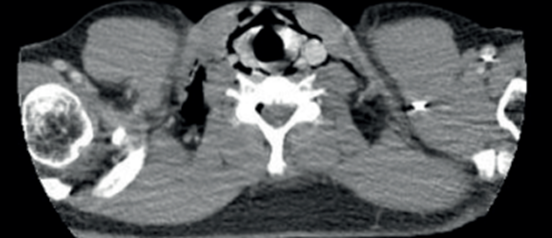

Figura1: En tomografía de tórax se observa extenso neumomediastino que diseca y se extiende a la pared derecha del hemitórax y hacia el cuello.

No se visualizan otras alteraciones parenquimatosas pulmonares (figuras2,3y4).

De la analítica a destacar: glóbulos blancos 16.000/mm3. Desarrolla insuficiencia respiratoria severa, tirajes altos y bajos, saturación de O2 67%, ingresando a unidad de cuidados intensivos. Se procede a intubación orotraqueal (IOT), murmullo alveolar ventilatorio disminuido, sibilancias en ambos tiempos respiratorios. Se conecta a asistencia respiratoria mecánica constatándose patrón de altas resistencias en vía aérea (RVA 35 m H20/l/seg, Pmax 80 cm H20), gasometría arterial con fracción inspirada de O2 de 100% revela insuficiencia respiratoria severa tipo 2, hipoxemia de 100 e hipercapnia de 149 mmhg. Se inicia sedoanalgesia continua (midazolam 1 mg/kg/hora, fentanilo 8 mcg/kg/hora), bloqueantes neuromusculares (atracurio 0,04 mg/kg/hora) por diez días. De forma complementaria dado el bronco espasmo severo y difícil adaptación a asistencia respiratoria mecánica, se recurrió a ketamina (0,3 mg/kg/min) por 72 horas. Se optimizó tratamiento broncodilatador (salbutamol y bromuro ipratropio inhalado de forma reglada) y corticoides sistémicos (hidrocortisona 100 mg cada 8 horas por 7 días), con descenso gradual en días consecutivos, logrando estabilización respiratoria con descenso progresivo de presiones en VA, mejoría progresiva del intercambio de gases. A 48 horas se realiza tomografía de control: disminución del neumomediastino y del enfisema subcutáneo, agrega zonas de enfisema en cara anterior del tórax por delante del manubrio esternal, en regiones maseteras y burbujas aéreas a nivel de espacios faringomucosos, prevertebral y neumorraquis (figuras5y6).